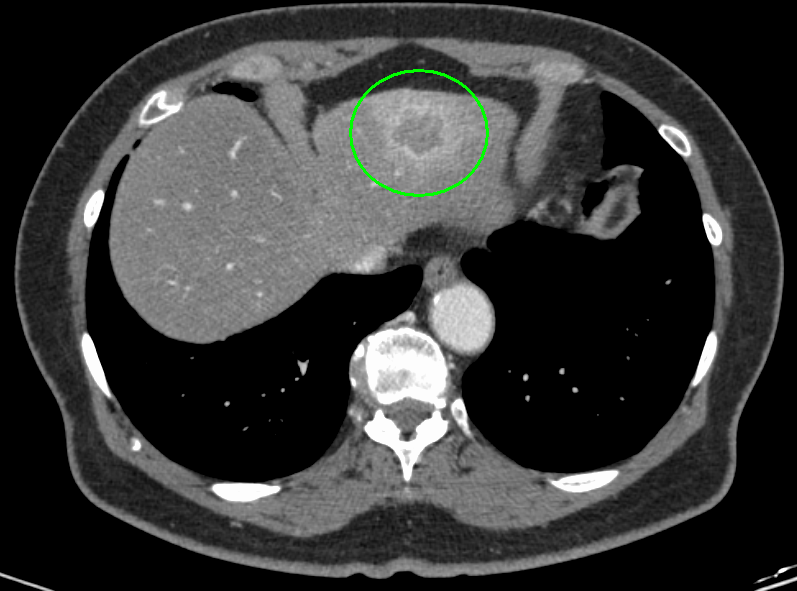

肝臓がんの検査としては、まず血液検査(肝機能検査、腫瘍マーカー検査)と超音波(エコー)検査を行います。必要により、CT検査もしくはMRI検査による画像検査も組み合わせて実施します。画像検査で良性/悪性の鑑別が難しい場合は、直接腫瘍組織を採取して調べる検査(針生検)を追加する場合もあります。

CT画像